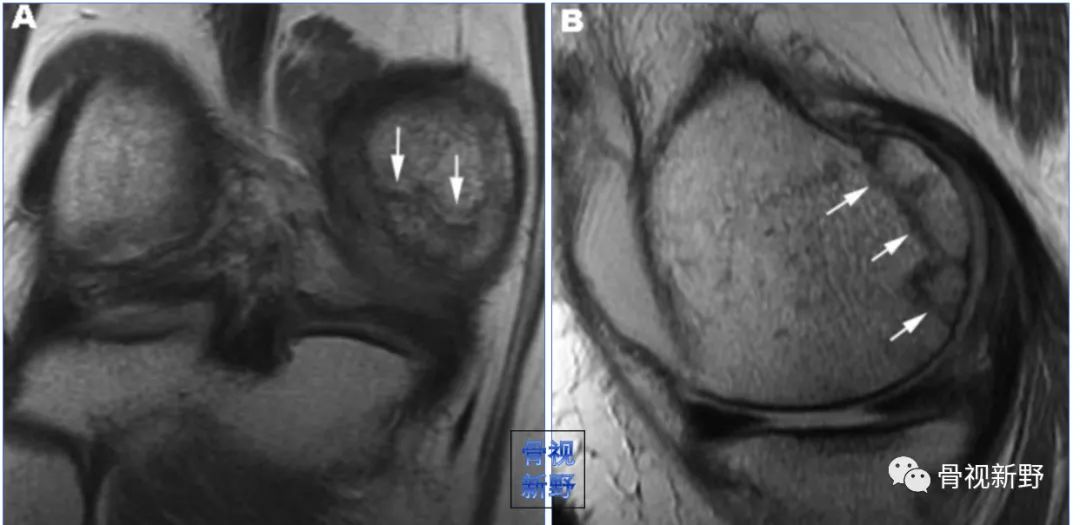

影像诊断:部分Hoffa骨折X线片不能提供明确的诊断,漏诊率较高。需要CT或MRI检查,并根据患者的病史、查体及影像学检查予以确诊。

MRI不但可发现隐匿性骨折,还可发现合并的软组织损伤